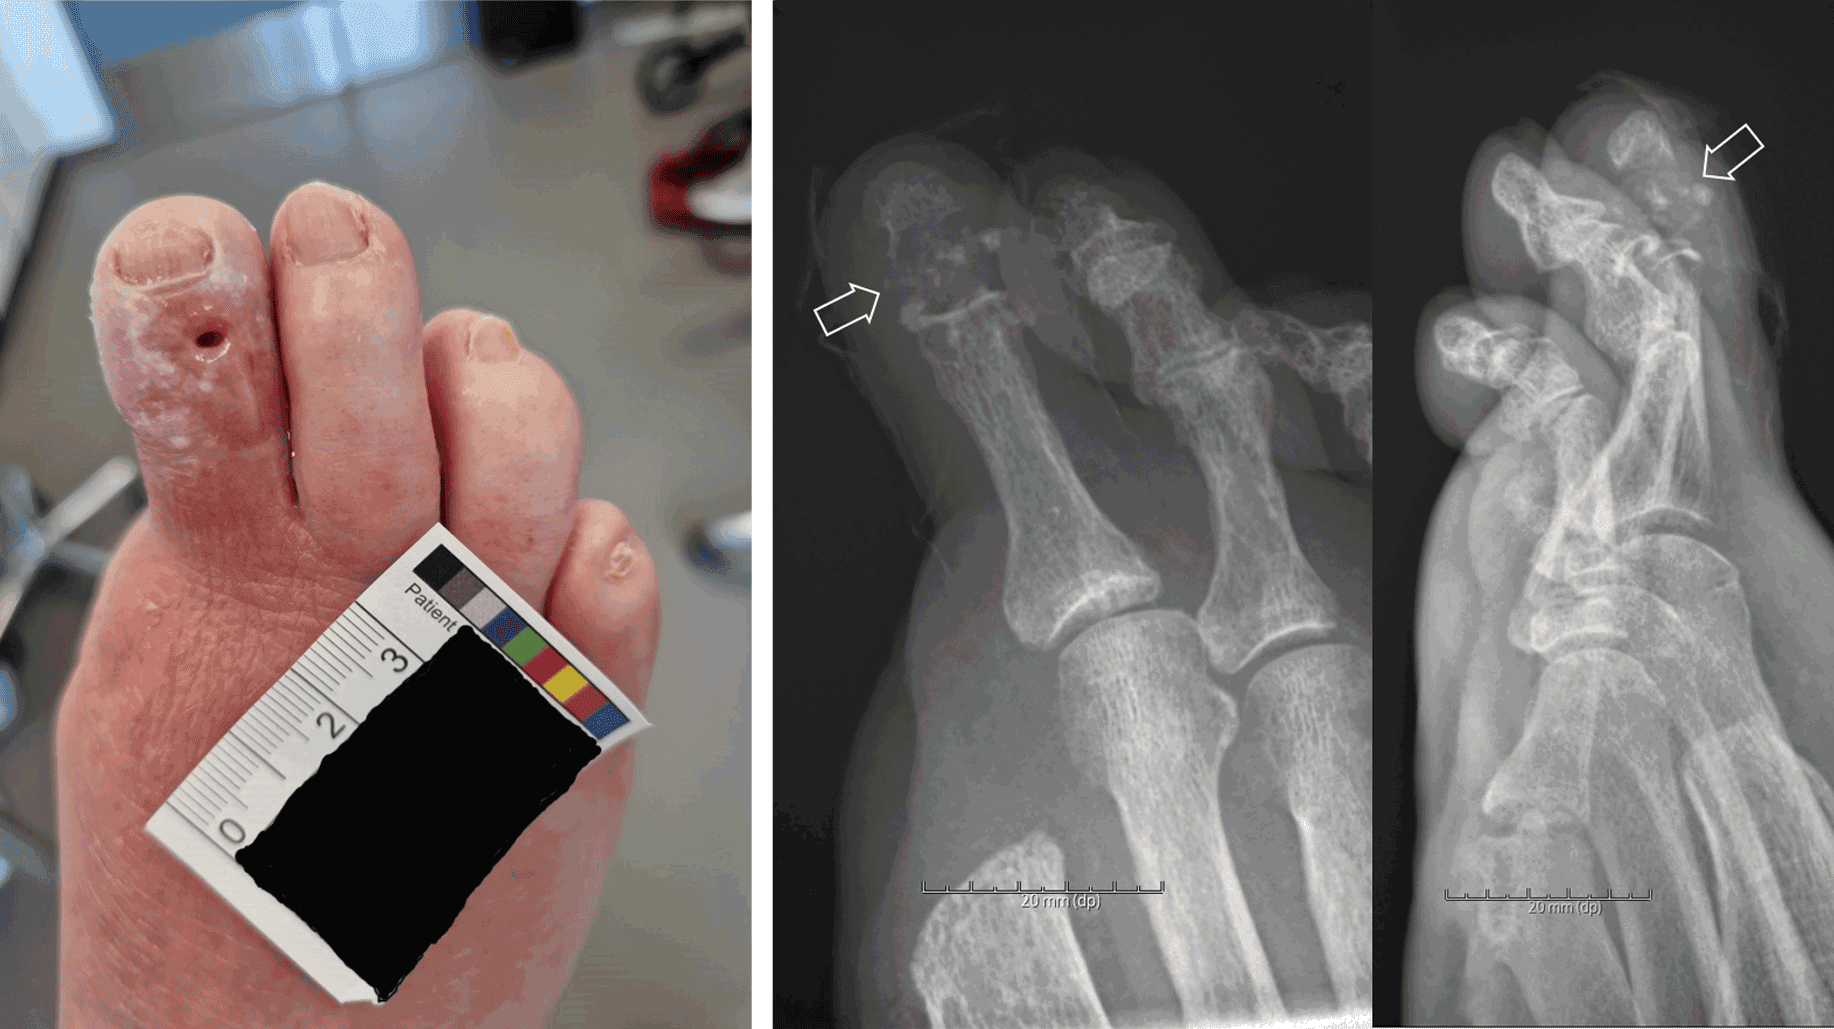

En 88-årig mand med DM2, hypertension, hyperkolesterolæmi, nedsat nyrefunktion og atrieflimren, og som var ikkeryger og uden alkoholoverforbrug, blev i 2005 undersøgt af neurolog pga. stikkende smerter under fødderne, men der var ingen tegn på neuropati. Patienten blev udredt i 2019 hos reumatolog pga. smerter i fødder, men uratsænkende behandling blev ikke iværksat. P-urat var i hele perioden 0,44-0,55 mmol/l. I 2012 havde han haft et forløb i diabetesambulatorium pga. sår over højre femte metatarsofalangeal (MTP)-led, som blev behandlet med sårpleje og langvarig antibiotikakur indtil opheling. Patienten var hos fodkirurg i 2017 med sår på højre anden tå, hvorfra der blev udtømt »tophusmateriale«. I 2022 opstod et nyt sår på højre første MTP-led, som blev behandlet med amputation af første tå. Der blev beskrevet »en del tophusmateriale« under operationen. Gentagne røntgenundersøgelser af fødderne viste fra 2012 tiltagende erosioner foreneligt med AU, men fortolket som infektion (Figur 1).

I 2024 blev patienten genhenvist til diabetesfodsårsambulatorium pga. recidiv af fodsåret på højre anden tå. Han gik sædvanligvis med træsko, der blev udskiftet til aflastende fodtøj. Der var ikke fejlstillinger eller kallositeter i foden. Distal blodtryksmåling viste, at højre tås tryk var kritisk lavt på 18 mmHg, og der var ingen fornyet karkirurgisk behandlingsmulighed. Fodstatus viste vibrationssans på 20 volt på begge fødder, bevaret stillingssans, ophørt kulde-/varmesans og følesans svækket, men ikke ophørt. Der blev i september 2024 udpresset grynet tandpasta-lignende materiale fra fodsåret, der for første gang blev undersøgt med polarisationsmikroskopi med påvisning af talrige nåleformede dobbeltbrydende uratkrystaller og dermed sikker diagnose af toføs AU. Patienten blev henvist til reumatolog, og uratsænkende behandling blev indledt. P-urat faldt fra 0,54 til 0,28 mmol/l efter to måneders behandling med allopurinol, men den kliniske effekt og svind af tophi kunne først forventes efter mange måneder.

Diagnosen AU er vanskelig, men røntgenbilleder kan give et godt fingerpeg i de sene toføse stadier med fodsår (Figur 1) [5]. Det er en god idé rutinemæssigt at undersøge for uratkrystaller, når der samtidig laves mikrobiologisk undersøgelse på ledvæske, operationsmateriale eller såroprensning. UL-undersøgelse og især dual-energy CT er andre muligheder for at påvise urataflejringer uden punktur.